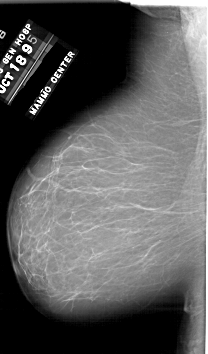

A_1748_1.LEFT_CC

LEFT_CC LINES 6601 PIXELS_PER_LINE 3691 BITS_PER_PIXEL 12 RESOLUTION 43.5 NON_OVERLAY

FILE: A_1748_1.RIGHT_CC.OVERLAY

TOTAL_ABNORMALITIES 1

ABNORMALITY 1

LESION_TYPE MASS SHAPE LOBULATED MARGINS CIRCUMSCRIBED

ASSESSMENT 3

SUBTLETY 3

PATHOLOGY BENIGN

TOTAL_OUTLINES 1

BOUNDARY